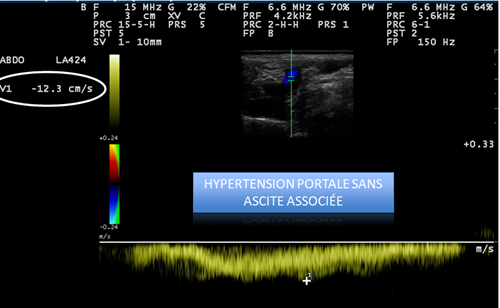

Absence d’ascite et de modification visible à l’échographie du système digestif.

À ce stade, on suspecte que l’hypertension portale mise en évidence ici puisse être à l’origine d’une hypoxie digestive et donc d’éventuelle manifestation par un ptyalisme.

- Hypertension portale